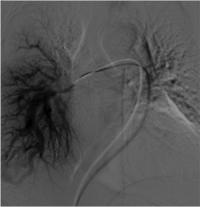

HHT is characterized by internal bleeding due to malformations of blood vessels in organs such as the skin, mucous membranes, lungs, intestines, liver, and brain. Symptoms can range from persistent nosebleeds and lesions to life-threatening complications, such as stroke or heart failure. The condition may require surgical intervention, highlighting the need for accurate screening and coordination of care between all specialists involved. In addition to treatment, the genetic component of HHT emphasizes the importance of genetic counseling to potentially identify other family members who may be at risk.

For patients like Emily Freda, who learned of her family history of HHT just as she herself was diagnosed with an arteriovenous malformation (AVM) in her lung, having the support of a dedicated, knowledgeable medical team is invaluable. "I had never heard of an AVM before and it sounded serious, but nobody in the ER could tell me who to call regarding treatment," said Ms. Freda. "I called the number on the CureHHT.org website the next day, and they put me in touch with Dr. Chheang's office. From my first appointment with her I felt so much calmer about the AVM and the fact that I too have HHT. I can't tell you the peace of mind I have knowing that I have Dr. Chheang on my side."